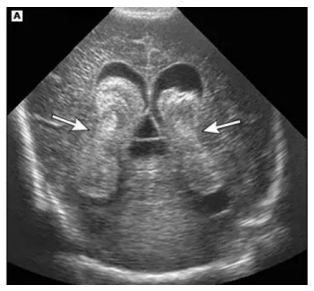

Ao realizar o exame ecográfico transfontanela de um

RN prematuro de 34 semanas, com anóxia perinatal,

você se depara com a seguinte imagem no plano coronal.

assinale a alternativa correta.